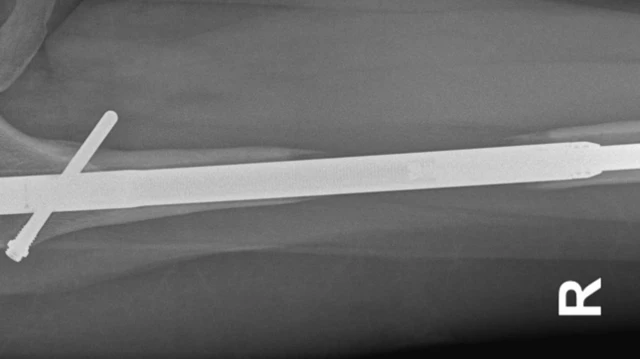

ਹੌਲੀ-ਹੌਲੀ ਦੋਵਾਂ ਹਿੱਸਿਆਂ ਵਿਚਾਲੇ ਲੱਗੇ ਧਾਤ ਦੇ ਇਸ ਰਾਡ ਦੀ ਲੰਬਾਈ ਵਧਾਈ ਜਾਂਦੀ ਹੈ, ਤਾਂ ਜੋ ਮਰੀਜ਼ ਦੀ ਲੰਬਾਈ ਵਧੇ।

ਅਪ੍ਰੈਲ 2017 ਵਿੱਚ, ਉਨ੍ਹਾਂ ਨੇ ਈਲੇਨ ਦੀ ਖੱਬੀ ਲੱਤ ਨੂੰ ਵੱਡਾ ਕਰਨ ਦੀ ਪ੍ਰਕਿਰਿਆ ਸ਼ੁਰੂ ਕੀਤੀ। ਇਸ ਦੌਰਾਨ, ਹੱਡੀਆਂ ਦੇ ਵਿਕਾਸ ਨੂੰ ਉਤੇਜਿਤ ਕਰਨ ਲਈ ਸੱਜੇ ਲੱਤ ਵਿੱਚ ਬੋਨ ਮੈਰੋ ਦਾ ਟੀਕਾ ਲਗਾਇਆ ਗਿਆ ਸੀ।

ਉਹ ਦੱਸਦੀ ਹੈ, "ਡਾ. ਗੁਈਸ਼ੇਟ ਨੇ ਮੈਨੂੰ ਦੱਸਿਆ ਕਿ ਜਦੋਂ ਉਹ ਮੇਖ ਕੱਢ ਰਹੇ ਸਨ ਤਾਂ ਉਹ ਟੁੱਟ ਗਈ। ਉਨ੍ਹਾਂ ਕੋਲ ਕਿਸੇ ਹੋਰ ਮਰੀਜ਼ ਦੀ ਮੇਖ ਸੀ ਜੋ ਉਹ ਮੇਰੇ ਪੈਰ ਵਿੱਚ ਪਾਉਣ ਵਾਲੇ ਸਨ। ਪਰ ਇਸ 'ਤੇ ਹੋਰ ਪੈਸੇ ਲੱਗਣੇ ਸਨ।"